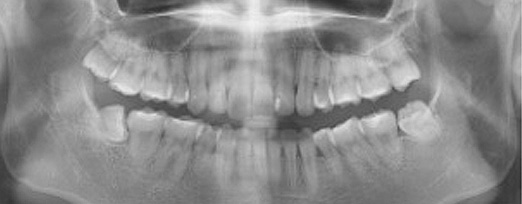

치주치료 전후사진

B

A